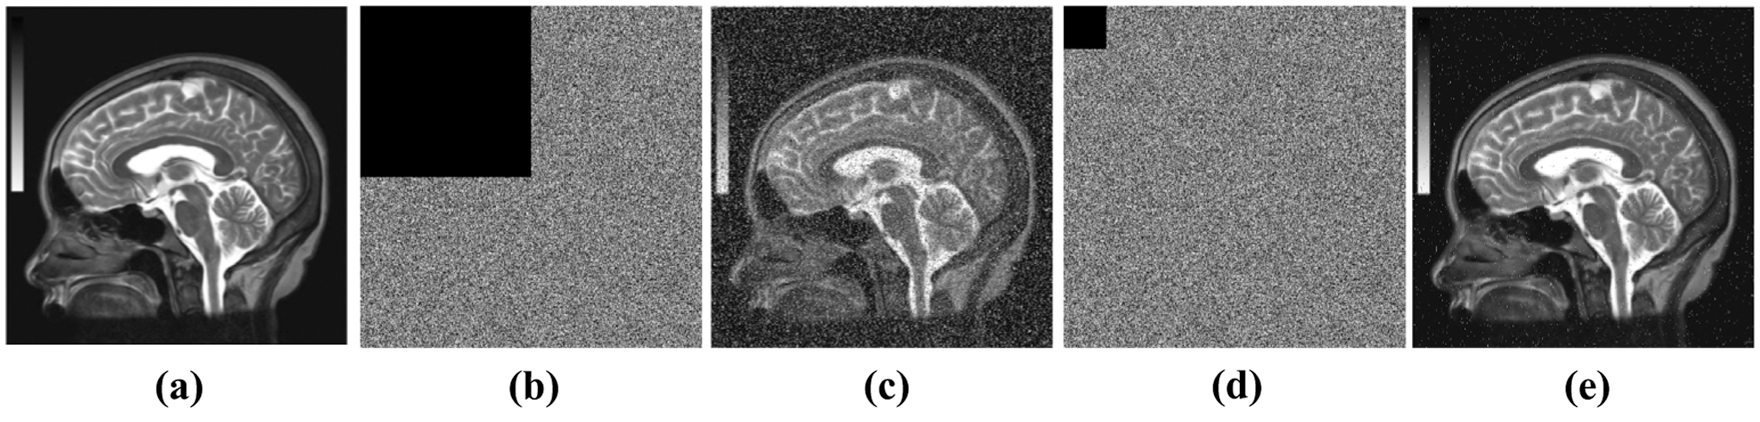

To analyze the robustness of the proposed framework against occlusion attacks, we perform the following test. A cipher image is occluded with a black block occupying

Tab. 2 presents a comparison between the robustness of the proposed framework and the relevant medical image encryption scheme in [28]. As evident from the results in Tab. 1, the values of the PSNR metric for the same encryption scheme depend on the choice of plain image. For the comparison to be fair, we must use the same test image used by [28], which is shown in Fig. 6. The result of the comparison demonstrates that the proposed framework is on par with related medical image encryption scheme [28].

Figure 5: Occlusion attack analysis for the proposed system (shown in (a) and (c)), in comparison to framework [1] without scrambling (shown in (b) and (d))

Figure 6: Image used for occlusion robustness. (a) plain image, (b) 1/4 occluded cipher image, (c) 1/4 ocluded decrypted image, (d) 1/64 occluded cipher image, (e) 1/64 decrypted image